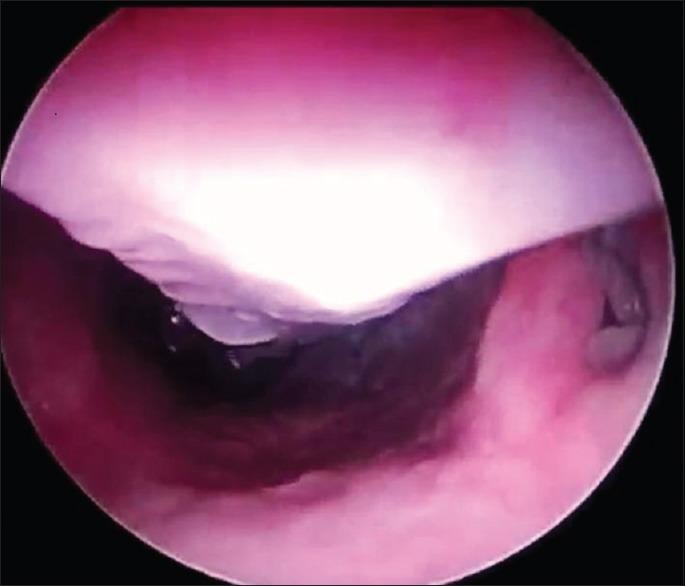

Surgically assisted rapid palatal expansion (SARPE) is one of the most common orthognathic surgery operations for the treatment of maxillary transverse deficiencies. Although this operation is considered technically simple and has low complication rate, predisposing factors can complicate the postoperative period. In this case report, fistula formation and aspergillosis after SARPE operation were presented.

外科辅助快速腭扩展术(SARPE)是治疗上颌横向发育不足最常见的正颌外科手术之一。尽管该手术在技术上被认为简单且并发症发生率低,但易感因素会使术后情况复杂化。在本病例报告中,介绍了一例外科辅助快速腭扩展术后瘘管形成和曲霉病的情况。